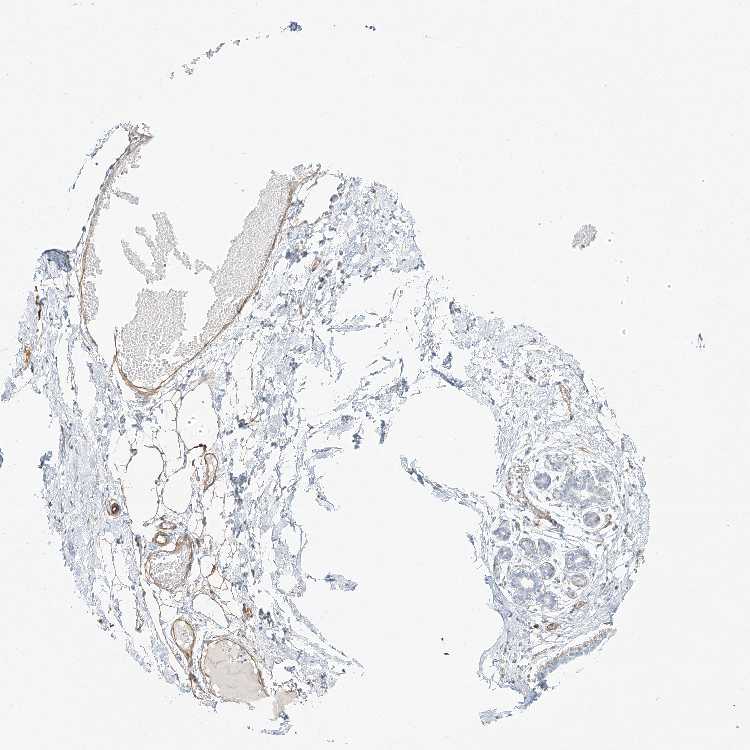

BREAST - Antibody stainingi

Antibody staining in the annotated cell types in the current human tissue is reported as not detected, low, medium, or high, based on conventional immunohistochemistry profiling in selected tissues. This score is based on the combination of the staining intensity and fraction of stained cells.

Each image is clickable and will lead to virtual microscopy that enables deeper exploration of all samples and also displays staining intensity scores, fraction scores and subcellular localization as well as patient and tissue information for each sample.

Antibody HPA031813Antibody HPA076571

Adipocytes MediumNot detected

Glandular cells Not detectedLow

Myoepithelial cells Not detectedNot detected